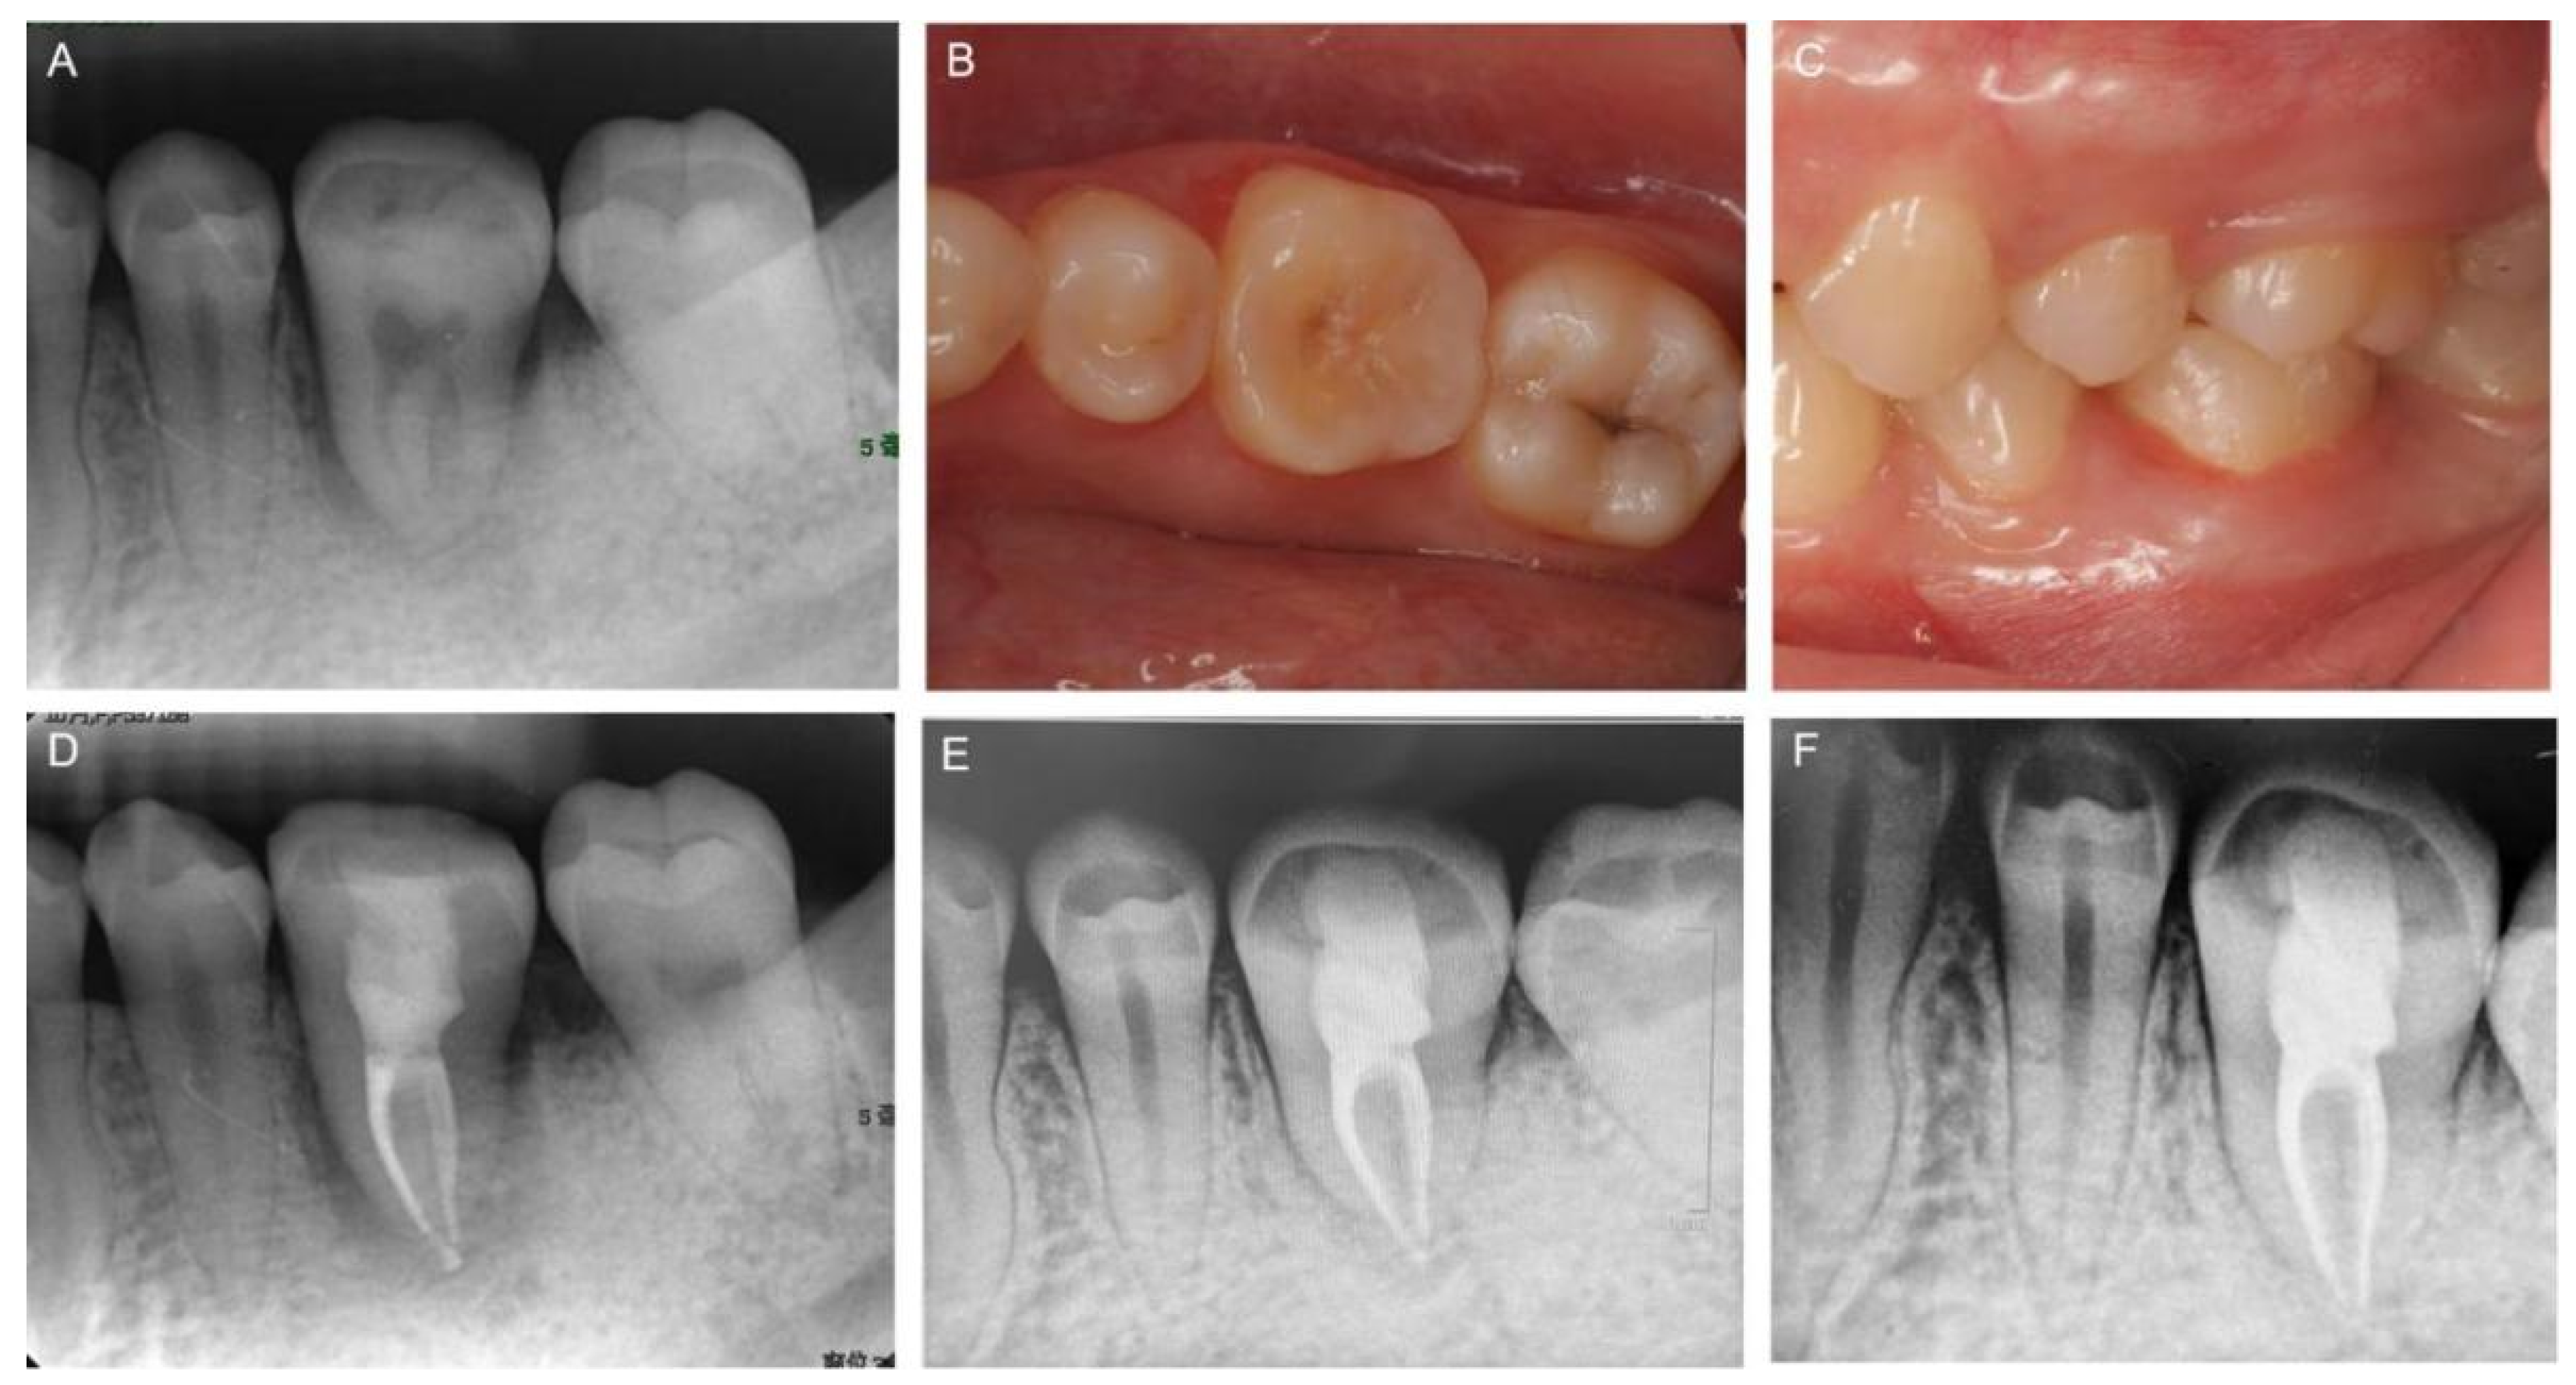

2. Case Report

2.1. Clinical Examination and Treatment Planning

3. Results